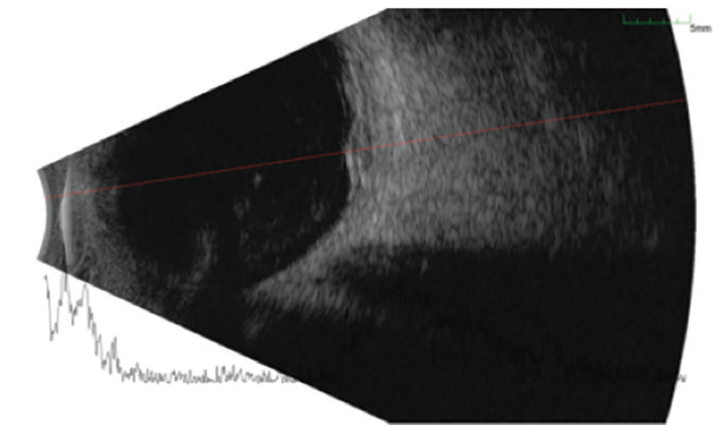

When the patient presented for his ocular oncology appointment, he had not developed any discomfort or pain in his eyes since his appointment with a referring physician that week. His VA was 20/100-1 OD and 20/60+2 in his left eye (OS). Posterior segment evaluation OD was significant for an elevated mass temporal to the macula, 4.5 by 8.0 disc diameters in size. Fundus photography of the lesion highlighted its orange color and size (Figure 1). Fluorescein angiography showed the mass infratemporal to the macula (Figure 2). Ocular ultrasound revealed an elevated posterior pole mass, 12 mm by 14 mm in size, with high internal reflectivity (Figure 3). Ultrasound A-scan demonstrated an area of increased reflectivity (Figure 4). The presumed diagnosis was choroidal metastasis from the patient’s active thyroid cancer.

Figure 3. Ocular ultrasound reveals an elevated 12 mm by 14 mm posterior pole mass.